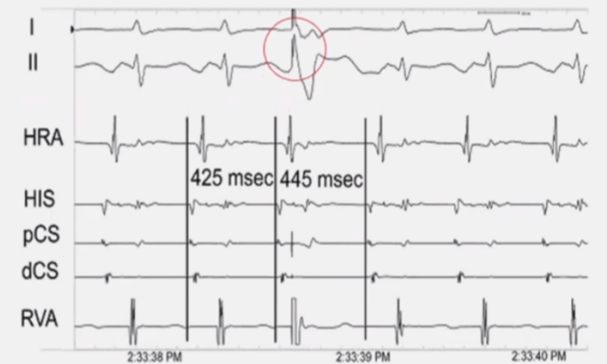

大折返性房速

体表心电图P波等电位线不清楚。围绕三尖瓣环的Halo导管和冠状实导管记录了双侧心房的心内激动,总的心房激动时间接近心动过速周长的90%。

局灶性房速

体表心电图P波等电位线相对清楚。围绕三尖瓣环的Halo导管和冠状导管记录了双侧心房的心内激动,总的心房激动时间小于心动过速周长的50%。